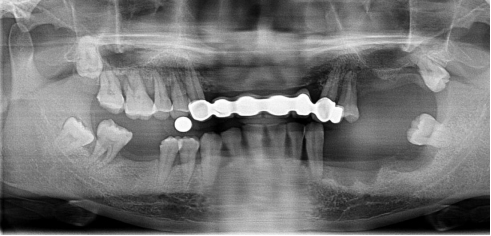

全口種植牙修復案例

病例簡介:

郭先生今年67歲,是位白手起家的成功企業(yè)家。早期忙碌的工作讓他疏于口腔保健,導致他上下牙列缺失。郭先生表示在二十年前在國外已經做過種植牙,但是近期來我院就診時其之前種植牙的種植體已經滑入到上頜竇內。

“患者前牙骨量不足,壁薄,后牙因手術取出以前的種植體導致了骨頭的大量缺損,所以需要植骨才能進行種植牙手術。種植需要避開手術后的骨缺失區(qū),所以對種植體的承受力和穩(wěn)定性要求較高,同時患者對美觀要求較高?!眲⒈笤淌谠诹私饬嘶颊叩男枨笈c口腔情況后為他進行了植骨手術,傷口愈合后,劉斌元教授為他進行CT掃描后確認可以進行種植牙手術。

手術成功結束,郭先生的全口牙齒全部種上,郭先生表示種牙后感覺很好,使用起來很方便:“終于吃上了我喜歡的堅果了!”